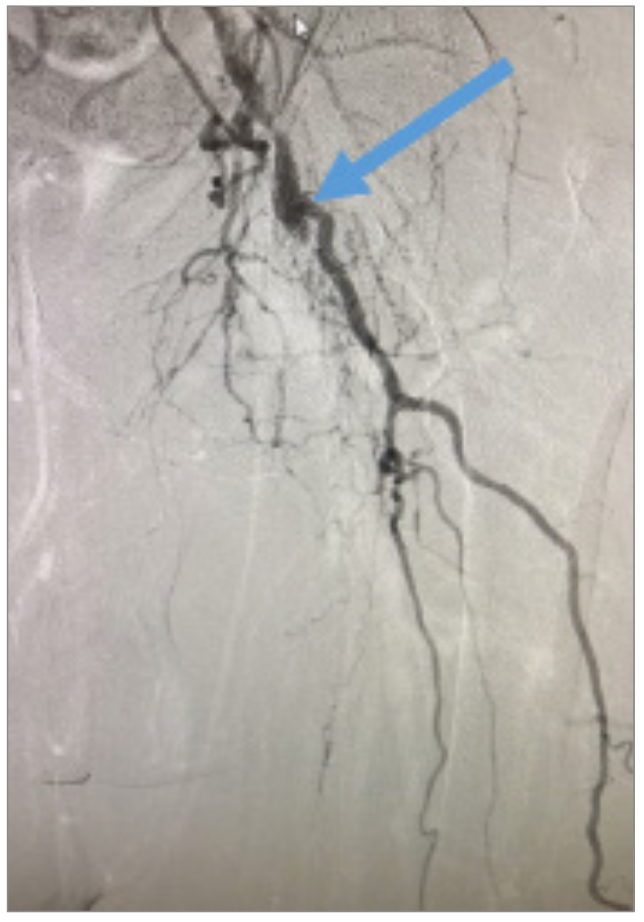

Angiography revealed that the superficial femoral artery (SFA) was occluded in the proximal segment with a short nub (Figure 1) and reconstituted in the mid segment by the profunda collaterals (Figure 2), before becoming reoccluded shortly thereafter and reconstituting in the distal SFA by the profunda collaterals (Figure 3). The P1 and P2 segments of the popliteal artery were patent, but the P3 segment had a short occlusion. The posterior tibial artery and peroneal artery also were patent.

A 6 French (Fr), 45 cm sheath was placed at the level of the left common femoral artery (CFA) from a right contralateral, retrograde CFA access. An .018 inch × 90 cm NaviCross microcatheter (Terumo) and a .014-inch Victory wire (Boston Scientific) were used to cross the CTO of the SFA, but entered a subintimal plane. The patient was prepared for direct left SFA access. An 18-gauge needle, stiff Glidewire (Terumo), and NaviCross microcatheter were used to gain ipsilateral, retrograde access of the left SFA. The CTO was crossed successfully with the stiff Glidewire. The stiff glidewire was switched with a .014-inch, 40 g Astato wire (Asahi Intecc). A 5 Fr, angled DAV catheter (Cook Medical) was then inserted via the right CFA access, and the Astato wire was maneuvered into the angled DAV catheter (Figure 4). The Astato wire was externalized through the “flossing technique” out of the contralateral femoral access. Percutaneous transluminal angioplasty (PTA) of the SFA lesion with a 4 × 150 cm balloon (Cook Medical) was performed through the contralateral retrograde access and exchanged for a.035-inch Quick-Cross catheter (Philips). A Runthrough wire (Terumo) was placed alongside the Astato wire and was extended past the SFA access site.